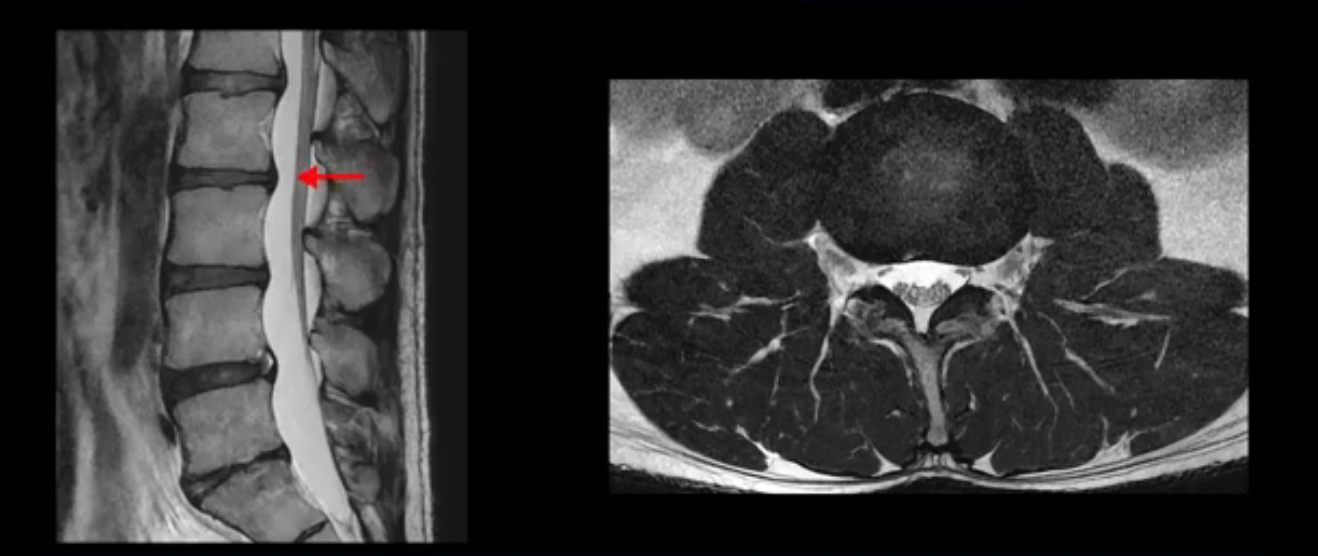

3번 4번도 마찬가지로 디스크상태 좋아 보이고 신경 눌림 전혀 없어 보입니다.

5번 1번 역시 가운데로 디스크 조금 밀려 나와있지만 신경 공간 넓이는 아주 넓어서 신경 눌림 있을 거라고 예상이 안됩니다.

추간공도 보시다시피 왼쪽, 오른쪽 전부 다 매우 넓어서 신경이 눌릴만한 부분이 전혀 보이지 않습니다.

앞서 1번 2번, 4번 5번, 5번 1번의 디스크가 찢어지고 조금 밀려 나온 게 최근에 찢어진 게 아니고 오래된 걸로 보인다고 말씀 드렸죠. 왜 그럴까요? 만약 급성으로 찢어진 것이라면 아주 심한 디스크성 통증이 있겠죠. 기침이나 재채기를 하면 심하게 아프고 허리를 조금만 구부리거나 비틀면 아주 날카로운 통증들이 생길 겁니다. 그런데 이분은 이런 증상이 전혀 아닙니다. 또 디스크의 밀려나온 정도도 전혀 심하지 않기 때문에 이분이 가지고 계신 양쪽 다리 저림, 특히 이분은 누워있을 때도 양쪽 발이 발가락까지 쑤신다고 하는데 이정도 디스크 때문에 그런 증상은 생길 수가 없는 겁니다. 이처럼 이분의 가벼운 디스크 탈출은 이미 오래 전에 진행되었고 섬유륜 자체는 이미 아문 상태인데도 디스크내장증을 진단받은 환자들 중에는 본인이 섬유륜 파열 환자라고 끝까지 믿는 분들이 많습니다. 다시 말하지만 디스크내장증이라는 진단을 받은 환자들을 보면 거의 전부 다 섬유륜 파열 증상이 아닙니다. 증상이 완전히 다릅니다. 진단이 애초에 잘못되면 어떤 치료를 받아도 좋아질 수 없습니다.